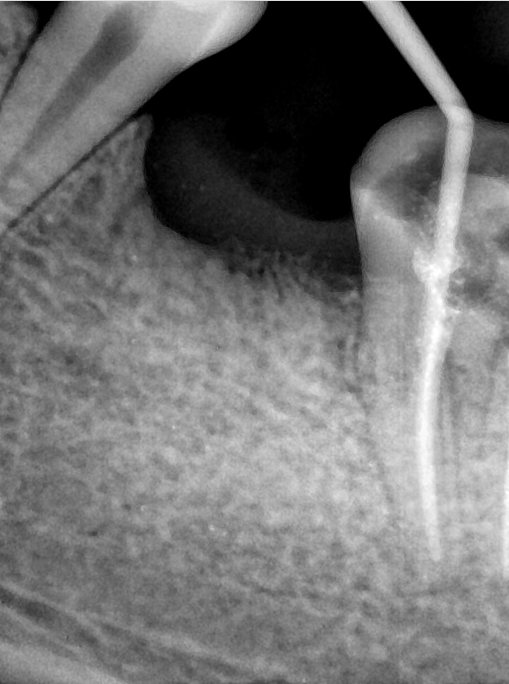

第二版算法问题测试

Updated: 2026-04-13(更新日期)

| 第一版 | 第二版 | 是否解决 | |

|---|---|---|---|

![]() | ![]() ![]() 边角识别有问题 龋齿识别不全 牙髓识别不全 | ![]() | 解决 |

![]() | ![]() 边角识别有问题 识别信息有误 自查(牙冠识别不全) | ![]() | 解决 |

![]() | ![]() ![]() 边角识别有误 大范围填充识别遗漏 | ![]() | 解决 |

![]() | ![]() 识别信息不全 | ![]() | 解决 |

![]() | ![]() ![]() 边角问题 牙胶识别不全 牙冠识别不全 | ![]() | 解决 |

![]() 换图片 | ![]() | ![]() 牙冠部分稍微白了一些就识别成小范围修补,部分判断异常 | 部分解决,修复类略敏感,牙冠部分稍微白了一些就识别成小范围修补,部分判断异常。 |

![]() | ![]() ![]() 牙冠识别不全 牙髓不全 根尖炎龋齿识别有误 | ![]() | 解决 |

![]() | ![]() | ![]() | 解决 |

![]() 换图片 | ![]() | ![]() | 解决 |

![]() | ![]() 牙冠识别有误 | ![]() | 解决 |

![]() 换图片 | ![]() ![]() 边角识别有误 | ![]() 修复类敏感 | 部分解决,图像过白,导致修复类判断异常。 |

![]() 换图片 | ![]() 牙冠识别不全 | ![]() 修复类敏感 | 部分解决,图像过白,导致修复类判断异常 |

结论:修复类出现了不鲁棒的情况,后续需要加入轮廓的扩充数据进行增强。